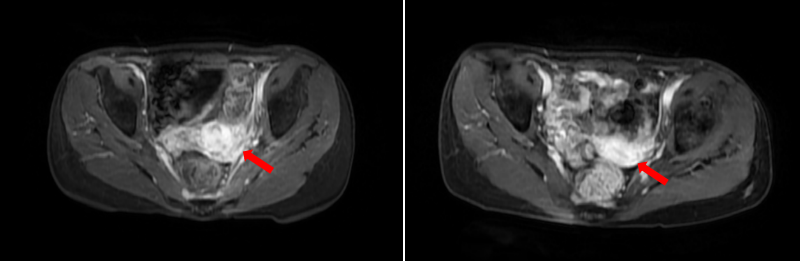

福建省肿瘤医院妇科肿瘤诊治中心是国家临床重点专科、福建省妇科恶性肿瘤精准治疗临床医学研究中心,同时也是国家第一批卵巢癌与宫颈癌规范诊疗质量控制试点中心。作为省内规模最大的妇科肿瘤综合治疗中心,年收治宫颈癌、卵巢癌、子宫内膜癌及外阴癌等妇科恶性肿瘤患者病例数均居省内各大医院首位。中心始终致力于将最新的科技成果造福于广大肿瘤患者,以高质量临床工作为基石,在临床转化研究领域不断取得新突破。近年来,不仅积极参与,更主动发起多项国际与全国多中心临床研究,目前国际、国内有关妇科恶性肿瘤最具前景的创新药物在中心均具有可及性。中心通过MDT汇集肿瘤外科、肿瘤内科、放射治疗科、影像科、病理科等多个学科专家,为患者提供规范全面的高质量手术与放射治疗等综合治疗体系,更是整合最新的靶向与免疫治疗策略,为晚期及复杂疑难妇科恶性肿瘤患者精准制定个体化治疗方案,让患者最大化的治疗获益。